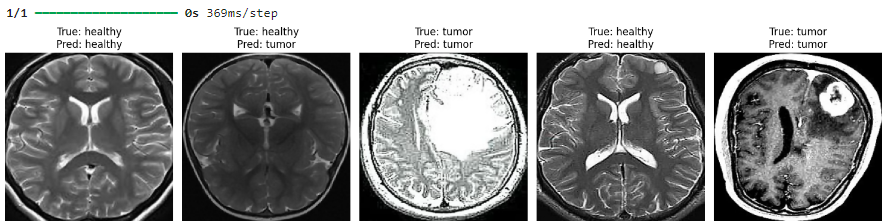

1. CNN for Classification: Using a fine-tuned VGG16 model, the system classifies MRI scans as tumor-positive or tumor-negative, ensuring high recall rates to minimize false negatives.

2. U-Net for Segmentation: A custom-built U-Net architecture pinpoints the exact tumor location, providing a visual overlay for clarity. The model employs Dice loss for enhanced accuracy in pixel-level predictions.